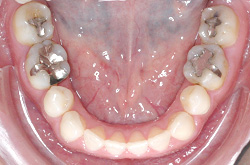

上あご・正面・下あご

before

after